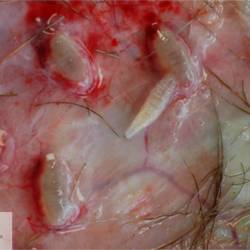

Peritoneum

Vasculitis

Vasculitis - Granulomatous

Feline infectious peritonitis